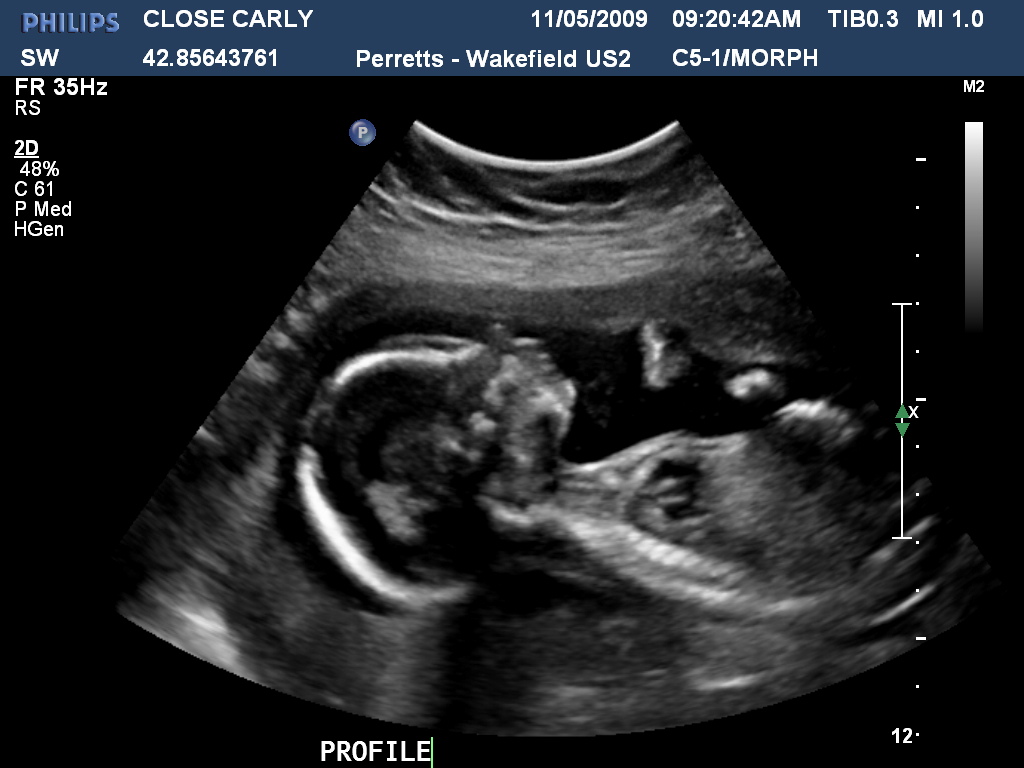

Wow how time flies! Carly is now 159weeks pregnant and now definately showing. Last week we had the first real scan and got to see hands and feet, the bub was quite active and gave the radiologist a hard time! Below are a few photos of both the bub and the expectant Mum to be!